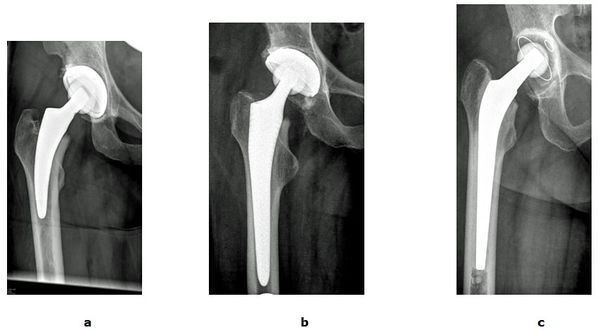

Abb. 4: Verschiedene Prothesentypen und Verankerungsmechanismen im Röntgenbild.

a Kurzschaftprothese mit Verankerung im Schenkelhals

b Anatomische Schaftprothese mit Verklemmung im Oberschenkelschaft

c Zementierte Verankerung bei schwerer Osteoporose